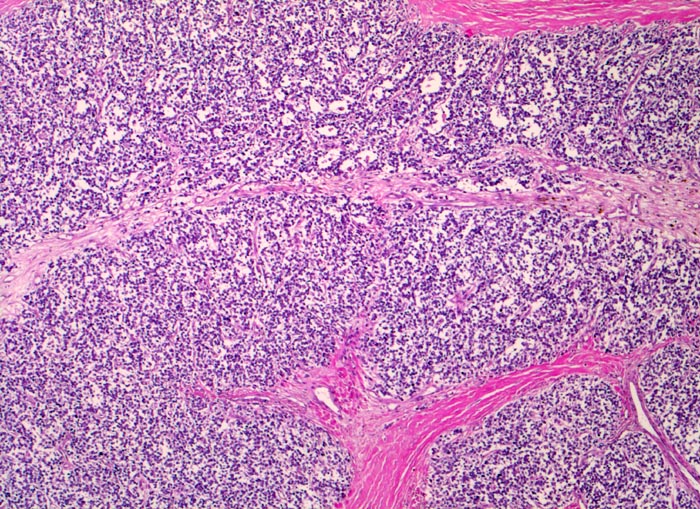

Ewing-Sarkom

Weichteile Bein

Monotoner Rasen kleiner runder blauer Tumorzellen durchzogen von bindegewebigen Septen.

Zunehmende Schmerzen im rechten Oberschenkel mit Weichteilschwellung- und Erwärmung seit mehreren Monaten. Keine Traumaanamnese. Klinisch wird zunächst eine Osteomyelitis vermutet.